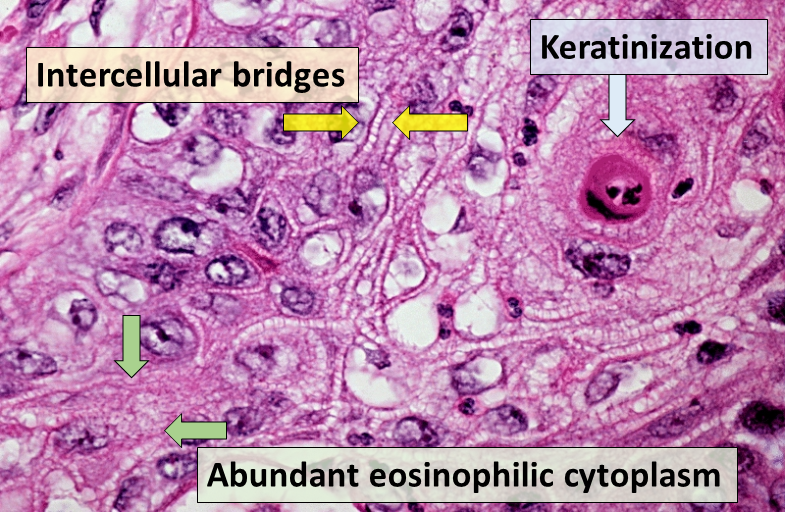

Squamous Cell Carcinoma of the Bladder

The second most prevalent type of bladder cancer is squamous cell carcinoma (SCC) of the bladder.

Squamous cell carcinoma (SCC) of the bladder is characterized by abnormal, accelerated squamous cell proliferation.

The normal bladder surface is not coated with squamous epithelium, hence this cancer develops against a backdrop of squamous metaplasia.